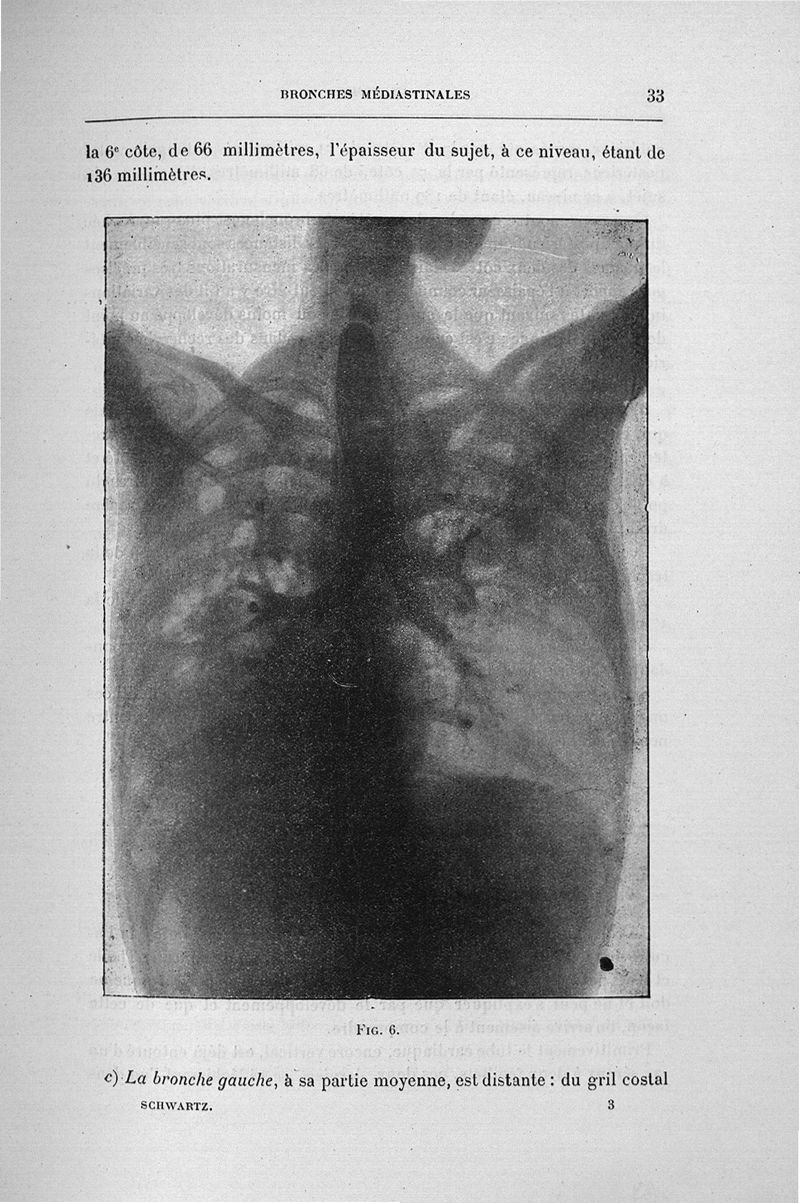

Schwartz, Anselme.

Titres et travaux scientifiques. 1910

Paris, G. Steinheil, 1910.